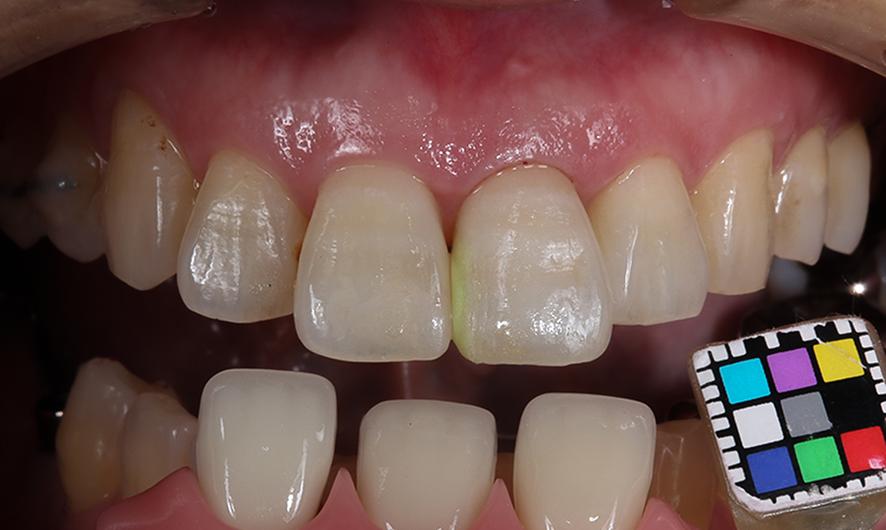

最終工程では、セラミック製の人工歯を作成しました。歯の色や形が自然に仕上がるまで、専用の電気炉で焼き入れを繰り返し、隣接する歯と調和するよう細かく調整しました。

最終的な歯の色合わせをしているところ。色が合うまで調整を繰り返します。

完成写真

最終的に、どこにインプラントがあるのか分からないほど自然な仕上がりとなりました。